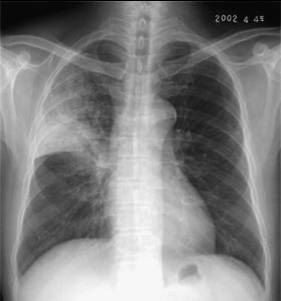

照片名称:高血压心脏病